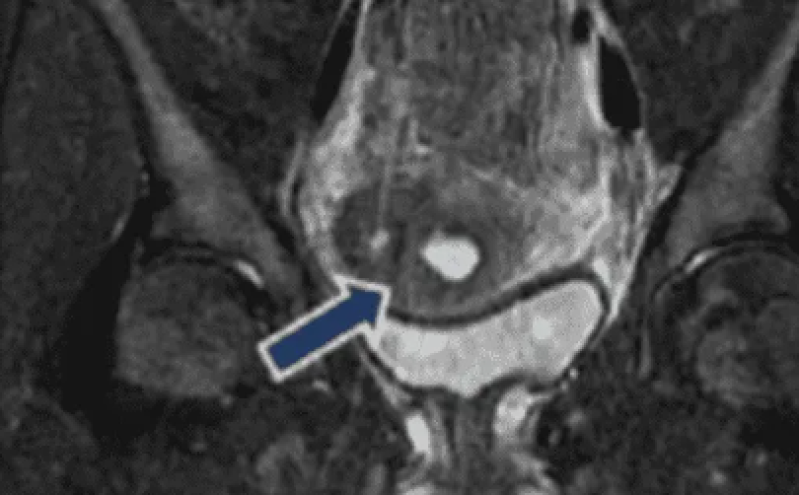

Después de insertar un catéter urinario, los médicos finalmente identificaron la fuente de su incontinencia: tenía un orificio entre la vejiga y la pared vaginal, conocido como fístula vesicovaginal en el lenguaje médico, que estaba causando que la orina se filtrara.